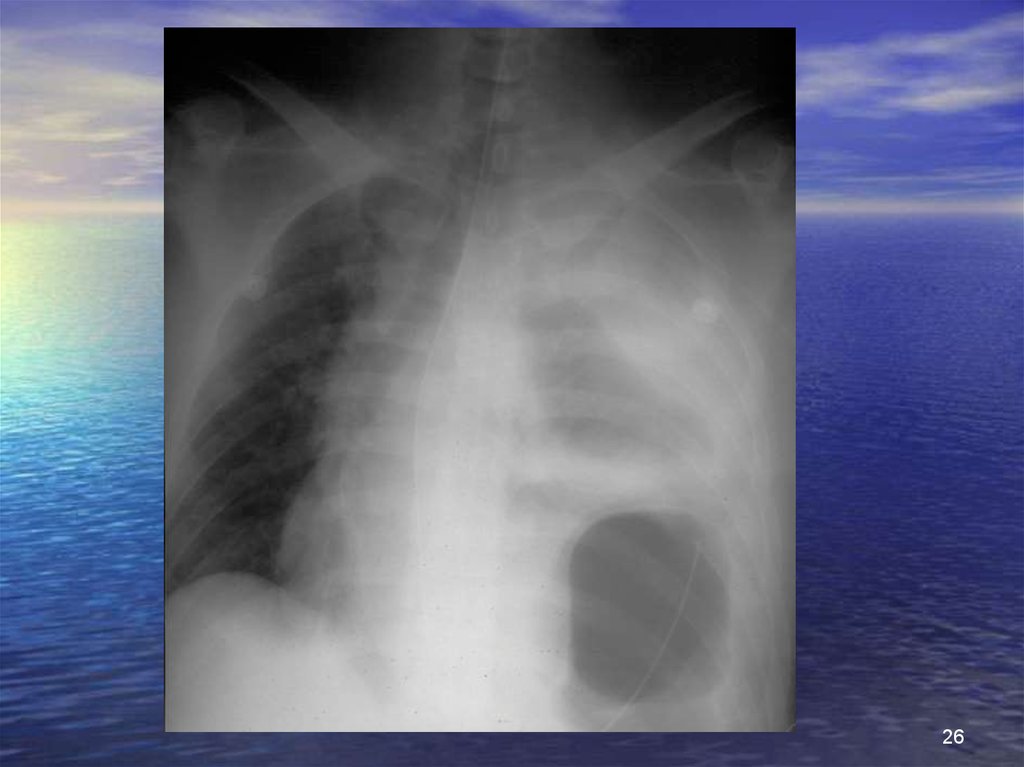

26.

26